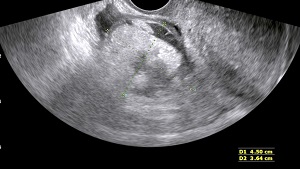

• Hemorrhagic Cyst: Bleeding with an ovarian cyst leads to formation of internal echoes, septae and blood clot.

• Findings: A well defined, well encapsulated fluid filled sac in ovary/ adnexal region. A clear fluid filled cyst is always benign. Presence of internal echoes is S/O blood/pus or substance with high molecular weight (which could be haemorrhagic cyst, chocolate cyst or dermoid).